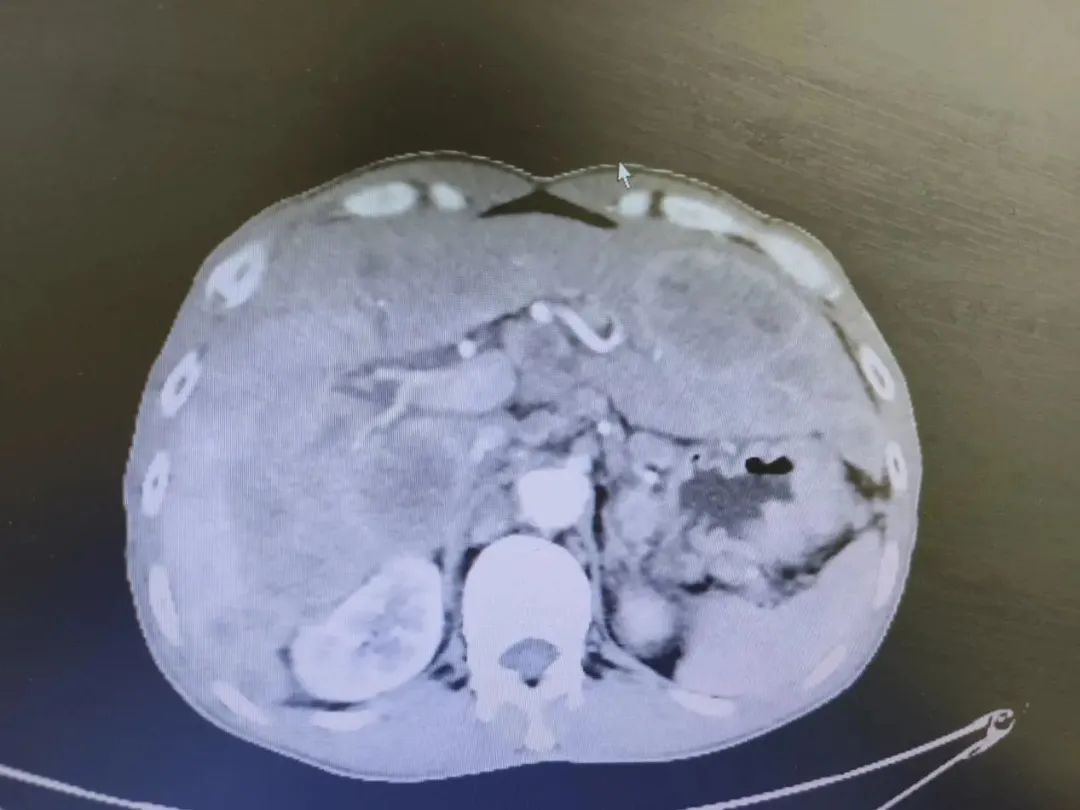

我院化疗前影像(2022年2月10日)